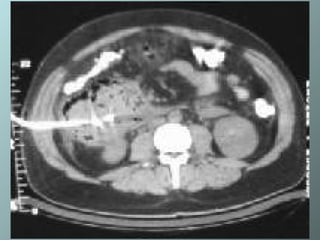

Necrosis pancreática: no se advierte intensificación del cuerpo del pancreas. Hay fluido peripancreático delante de la cabeza del páncreas

Necrosis pancreática

Absceso pancreático: colección heterogenea relativamente bien circunscrita conteniendo burbujas de gas dentro de la cabeza. La colección fue drenada con 1 cateter 12 Fr con cola de chancho